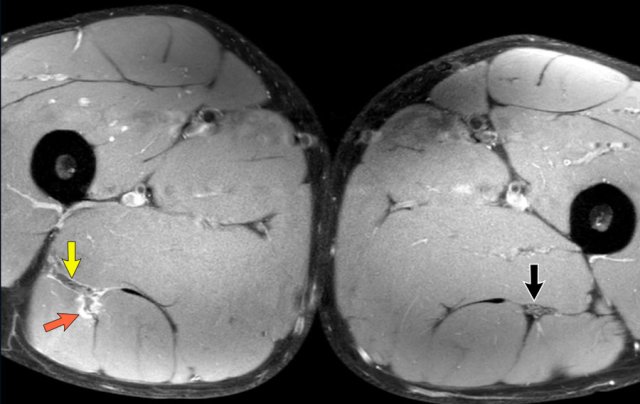

DOMS

In this patient, subtle muscle edema in the semitendinosus was seen, diagnosed as DOMS - delayed onset muscle soreness (arrow).

Both length of edema and distorted tendon are measured and noted in the report.

In this case, biceps femoris tendon injury was classified as grade 3 partial injury, since the length of the edema is > 15cm (white dotted line) and the length of the distorted tendon is > 5cm (yellow dotted line).

This image shows a partial injury of the conjoined tendon of the right leg (yellow circle).

There is a large amount of surrounding hematoma in the muscle and alongside the fascia.

The edema surrounds the ischiadic nerve (yellow arrow), which can lead to neuropathy.

However there is a poor correlation between the MRI findings and the symptoms of the patient.

In this case, the partial injury is less pronounced. Still, the ischiadic nerve is enlarged and flattened due to the injury edema.

All features of possible nerve involvement (nerve enlargement, flattening, nerve edema, surrounding edema or surrounding fibrosis) are noted.